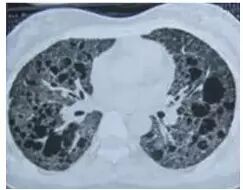

肺磨玻璃影(GGO,ground glass opacity)在胸部 CT 表现为密度轻度增高的云雾状淡薄影/圆形结节,样子像磨砂玻璃一样,所以叫磨玻璃影。

GGO 可以是弥漫性散在生长,也可以仅聚集在局部,看起来像一个小磨玻璃结节。一般而言,弥漫性生长的多数是良性病变,局灶性生长的容易不好。

1. 肺泡蛋白沉积症

患者的肺像铺路石一样

弥漫性的 GGO